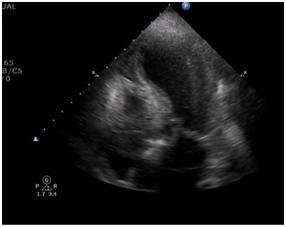

Transthoracic echocardiogram at admittance

After admittance, the patient underwent a transthoracic echocardiogram where we observed a left ventricle outflow tract gradient of 91 mmHg, as well as apical dyskinesia (Figure 2 & 3).

Figure 3 Left ventricle apical dyskinesia as seen with a 4 chamber apical view.